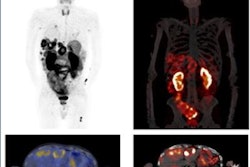

Treating formerly untreatable cancers. Theranostics -- a personalized approach to treating cancer using diagnosis and therapy as part of treatment -- is a hot topic, and recent innovations in molecular imaging technology are now helping clinicians realize its promise. For prostate cancer specifically, in just one exam, doctors can diagnose and treat cancer at a stage so advanced it had previously been considered untreatable.